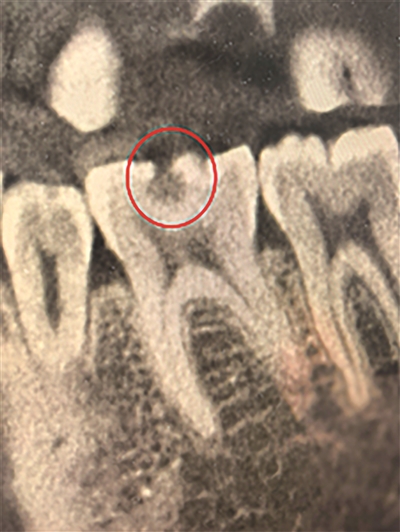

接近牙神经的龋洞 医院供图

杭州的李女士近日捂着半边脸来到我的门诊,经检查,她的牙齿已有深龋洞波及牙神经,必须做根管治疗。

无糖碳酸饮料里的酸,会直接酸蚀牙釉质导致 “牙齿脱矿”,破坏力不输糖;果干黏稠、糖分高,特别容易粘在牙齿缝隙里,成了细菌滋生的温床。这些“隐形酸”与“隐形糖”悄然损害牙齿,待出现冷热刺激痛时,龋坏往往已深达牙齿内部。

最后,感染深入牙髓,引发剧烈疼痛。若仍不及时处理,细菌将进一步感染牙髓(即牙神经),导致牙髓炎,甚至波及根尖周围组织。此时常伴剧烈疼痛,需进行根管治疗(俗称“杀神经”),牙齿结构及功能将永久受损。